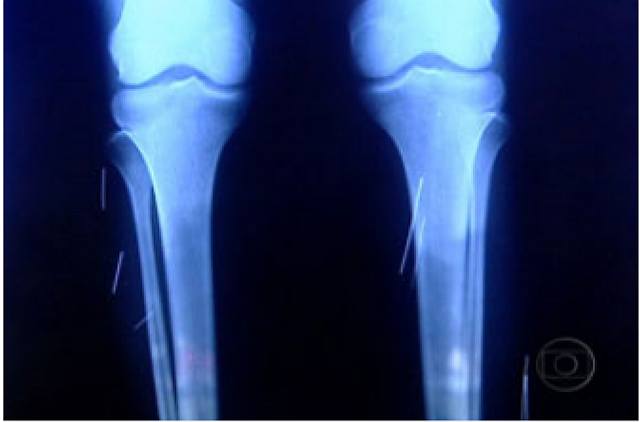

A Polícia Civil do Distrito Federal investiga o caso de uma jovem de 21 anos que tem agulhas e grampos espalhados pelo corpo. Ela foi internada no dia 15 de janeiro em um hospital de Taguatinga, cidade próxima à Brasília, com pneumonia e infecção no fígado. Nesta segunda-feira (3), o diretor do hospital, Joaquim Pereira, divulgou radiografias que revelam a existência dos objetos nos braços, glúteos e pernas da paciente.

A jovem passou nove dias internadas na Unidade de Terapia Intensiva (UTI) e só depois de três meses a possível causa das dores foi identificada. "Como persistiram alguns sintomas houve a necessidade posterior de examinar o corpo todo", explicou Pereira.

No entanto, a jovem continua com dores na barriga. Segundo os médicos, é possível que os sintomas tenham relação com objetos metálicos ainda não identificadas. "Pode existir algum corpo estranho dentro do abdome ainda não identificado. Vamos investigar", disse o diretor do hospital.